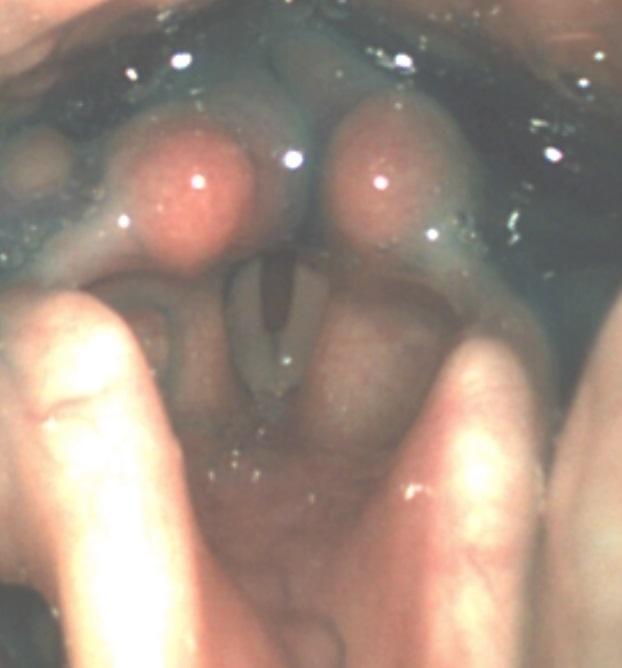

Angefärbte Milchreste auf der Innenseite des Kehldeckels bei einem Säugling.

Penetration und Aspiration von angefärbtem Brei bei einem Kleinkind.